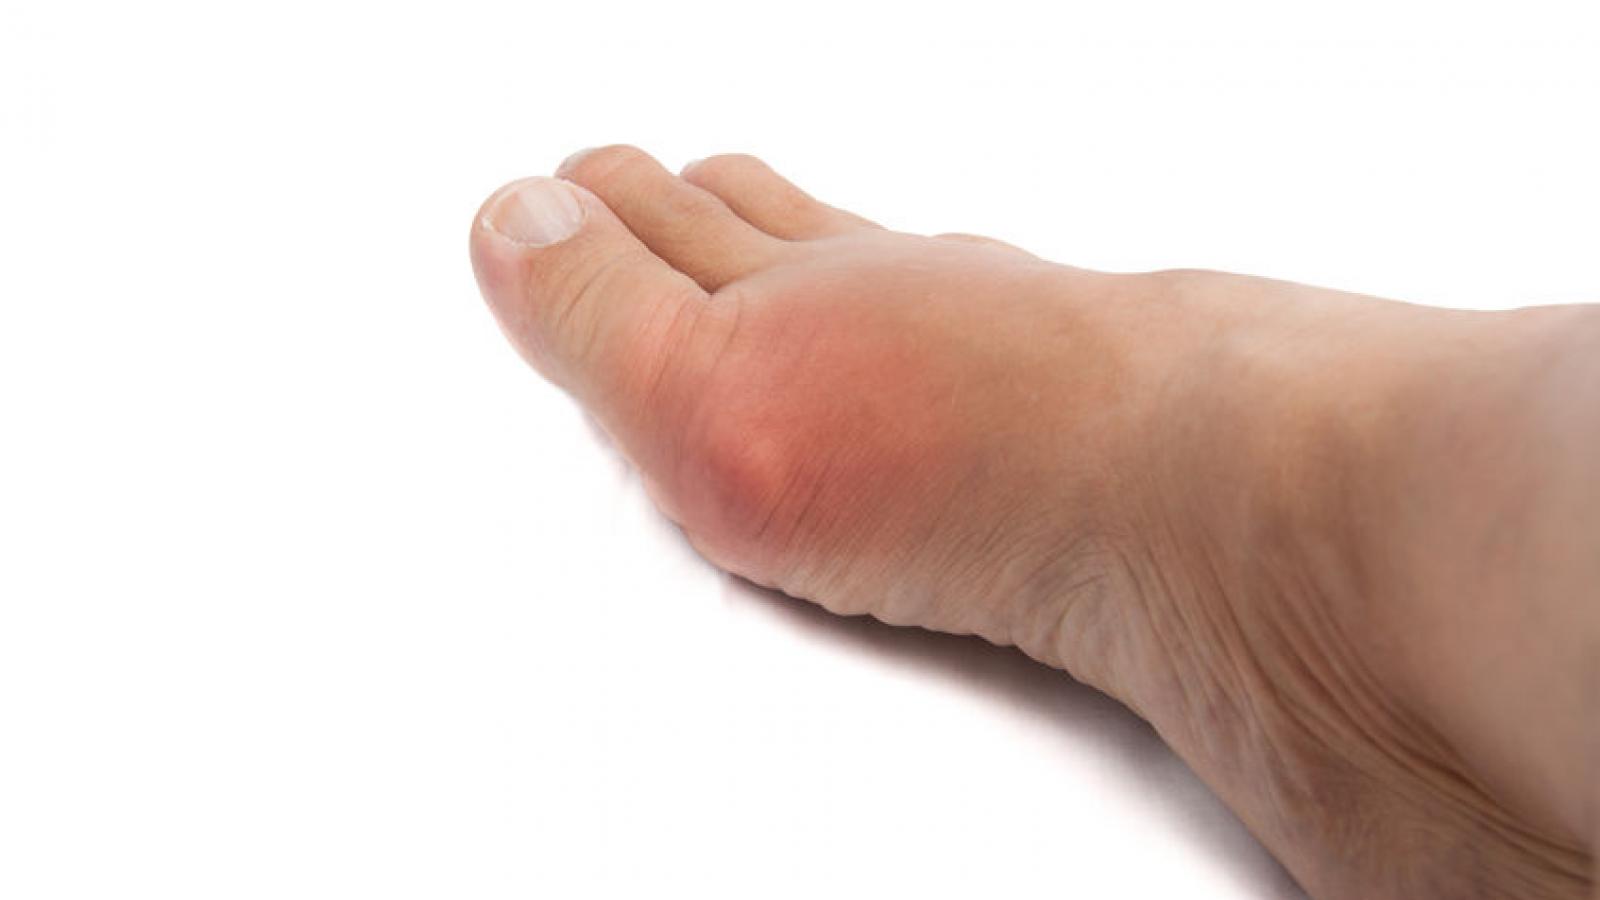

Gout

In a cross-sectional study of US adults, gout was more prevalent in black adults compared to white adults; possibly explained by sex-specific dietary differences and social determinants of health and clinical factors.

A large case-control study showed that gout patients who experienced a cardiovascular (CV) event were more likely to have had a recent (< 120 days) gout flare compared to those without CV events. This study sought to investigate the temporal association between gout flares and cardiovascular events in a gout cohort.

Despite updated gout management guidelines from European (EULAR) and British (BSR) societies, treatment of gout is suboptimal with regard to the use of urate-lowering therapy (ULT) and normalizing serum uric acid (< 6.0 mg/dl) levels.

Urate lowering therapy (ULT) is the backbone therapy for long-term gout treatment and maintenance, but real-world gout management is often imperfect and suboptimal.